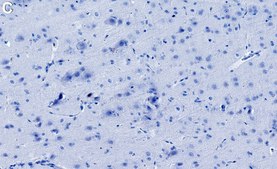

Evaluated by Immunohistochemistry (Paraffin) in rat cerebral cortex tissue sections.

Immunohistochemistry (Paraffin) Analysis (IHC(P)): A 1:100 dilution of this antibody detected CACNG8/TARP in rat cerebral cortex tissue sections.